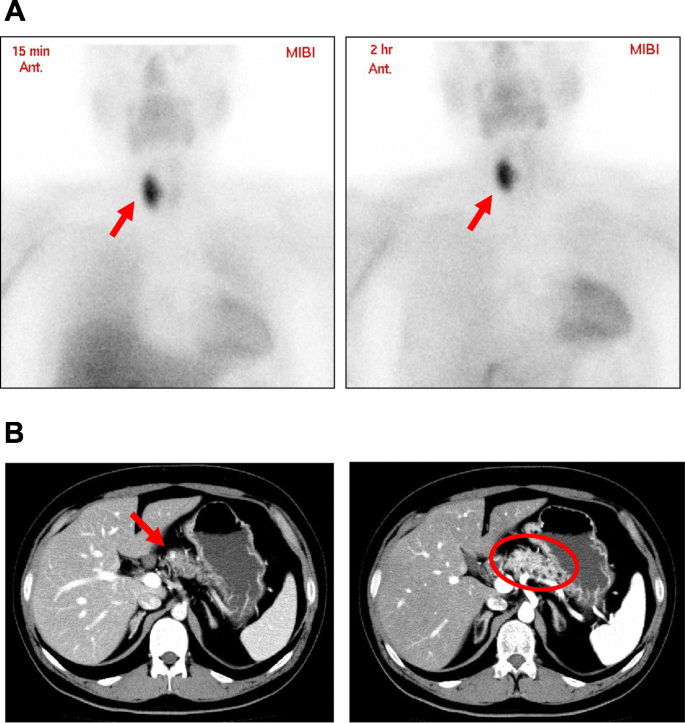

A 28-year-old man noticed the decreased visual acuity of both eyes and visited our institution. Since he was diagnosed as visual disturbance and brain computer tomography (CT) showed a mass in the pituitary fossa, he was hospitalized in our institution. On admission, his height and body weight were 171.4 cm and 83.7 kg. Blood pressure and heart rate were 113/63 mmHg and 63 bpm. Vision: (right) 30 cm manual valve, (left) 0.06. Field-of-view range: (right) nasal hemianopia, (left) normal. In contrast-enhanced brain magnetic resonance imaging (MRI), suspected neoplastic lesion was observed in the pituitary fossa (Fig. 1 A). Its maximal diameter was approximately 50 mm. It was a mixture of solid and cystic lesion which seemed to be hematoma. Invasion of the cavernous sinus and compression of the optic nerve were confirmed. In addition, large elastic mass was palpable in right cervical region, and the mass was isoechoic in neck ultrasonography (Fig. 1B). Intact-parathyroid hormone (PTH) level was high (273 pg/mL) and hypercalcemia (Ca, 12.1 mg/dL) were observed. Hyperprolactinemia (prolactin, 3,794.0 ng/mL) (normal range: 4.29–13.69 ng/mL) was also observed. Other endocrine hormone levels were within normal range as follows: ACTH, 59.9 pg/mL (7–63 pg/mL); cortisol, 13.5 µg/dL (7.07–19.6 mg/dL); DHEA-S, 388 µg/dL (85–690 mg/dL); GH, 0.08 ng/mL (0-2.47 ng/mL); IGF-1, 177 ng/mL (114–315 ng/mL); TSH, 1.90 µIU/mL (0.5-5.0 mIU/mL); FT3, 3.12 pg/mL (2.3–4.3 pg/mL); FT4, 0.52 ng/dL (0.9–1.7 ng/dL); LH, 0.8 mIU/mL (0.79–5.72 mIU/mL); FSH, 2.0 mIU/mL (2.0-8.3 mIU/mL); testosterone, 0.34 ng/mL (1.31–8.71 ng/mL). Hepatic dysfunction and dyslipidemia were observed: AST, 53 U/L; ALT, 102 U/L, γ-GTP, 69 U/L; LDL cholesterol, 145 mg/dL; HDL cholesterol, 44 mg/dL; triglycerides, 355 mg/dL. Neck ultrasonography showed two parathyroid tumors which maximal diameters were 38 mm and 14 mm, respectively (Fig. 1 C). In 99mTc methoxyisobutylisonitrile (MIBI) scintigraphy, MIBC accumulation was observed in the neck lesion at 15 min and at 2 h which was thought to be the accumulation in the parathyroid lesion (Fig. 2 A). Furthermore, contrast-enhanced abdominal computer tomography (CT) showed a small tumor in the pancreas head (diameter: 5 mm) and multiple fat density lesions in the whole pancreas (Fig. 2B). These lesions were thought to be multiple abnormal fatty deposits in the pancreas. Various pancreatic hormone levels were almost within normal range as follows: glucagon, 137 pg/mL (reference range: 70–174 pg/mL); gastrin, 213 pg/mL (30–200 pg/mL); insulin, 18.4 µU/mL (2.2–12.4 µU/mL); trypsin, 340 ng/mL (100–550 ng/mL).

(A) In 99mTc MIBI scintigraphy, MIBC accumulation was observed at 2 h as well as at 15 min in neck lesion which was thought to be parathyroid lesion (arrows in both panels). (B) Contrast-enhanced abdominal CT. Small tumor (diameter: 5 mm) was observed in the pancreatic head (an arrow in left panel). Multiple fat density areas were observed in the whole pancreas (a circle in right panel)